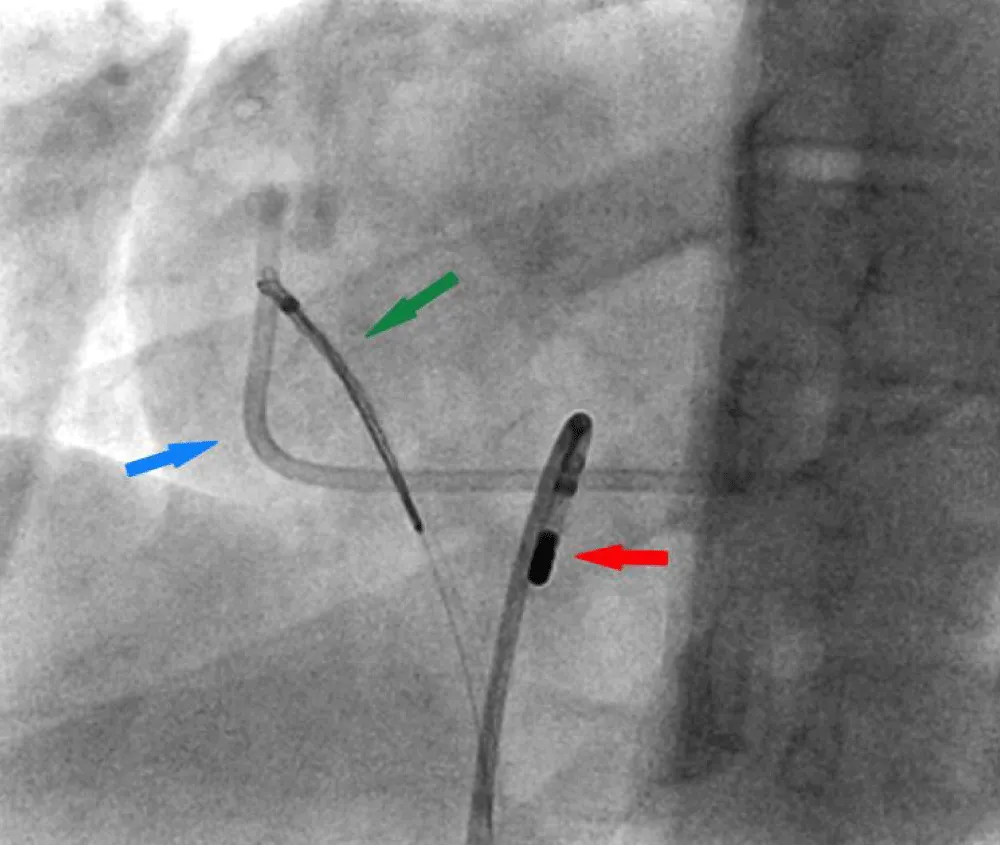

Therefore, further retrieval attempts using multiple catheters to hook the port over the tricuspid valve were unsuccessful. Finally, a navigational electrophysiology steerable catheter was used to hook the port over the tricuspid valve (Figure 3 and Video 1 Click here.

Figure 3: Right Heart catheterization shows a Navigational steerable catheter hooking the port and disengaging it from the coronary sinus. Fractured Port (blue arrow), Navigational steerable catheter (red arrow), Snare (green arrow).